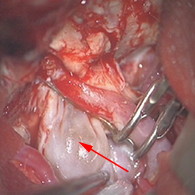

<実際の手術所見>

<手術所見>

手術で血管の内部で肥厚した内膜を除去する(内膜剥離術)。